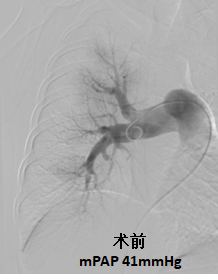

慢性血栓栓塞性肺动脉高压患者肺动脉残余血栓堵塞部分血管引起肺动脉高压,应用球囊扩张手术治疗可以明显改善被堵塞血管的血流,降低肺动脉压力,大部分患者胸闷气短症状完全改善,甚至可以恢复正常生活。